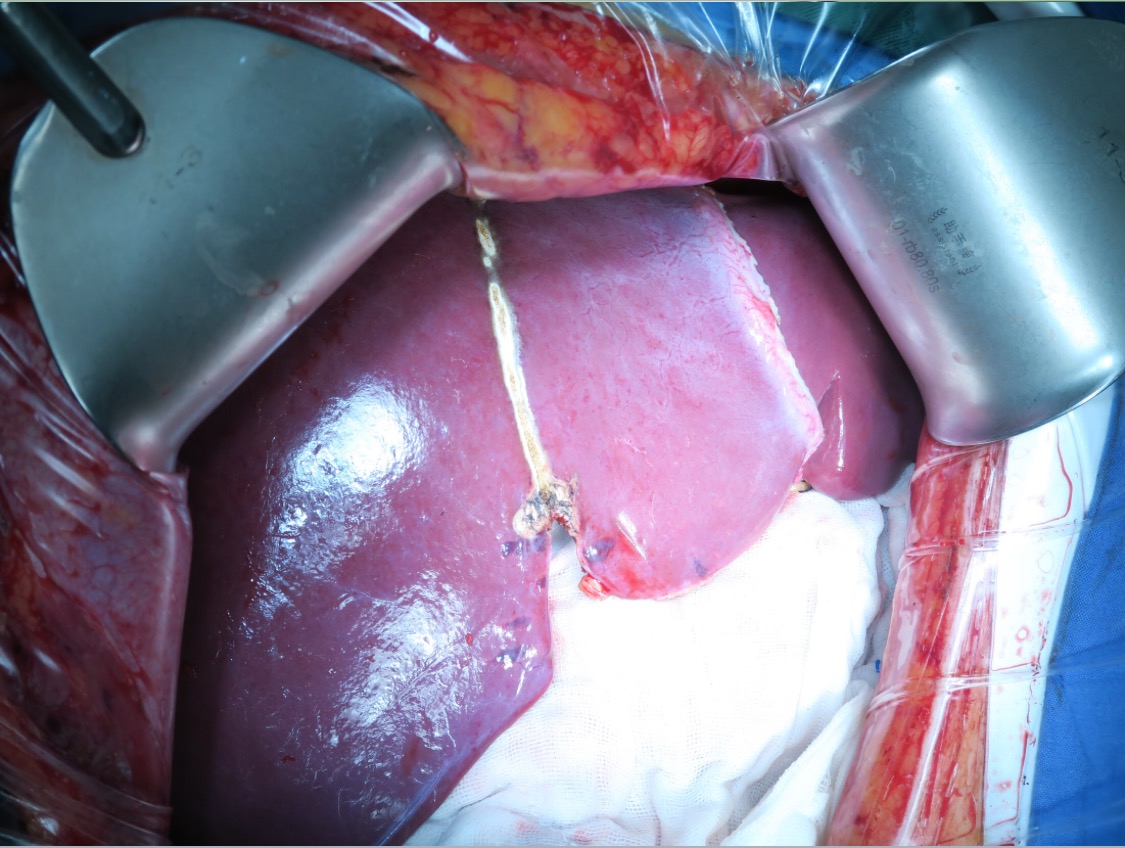

2019.09.18 北肿肝胆外一科邢宝才教授团队在全麻下行肝部分切除(IV段)、肝门淋巴结清扫、胆囊切除术。

术中情况:

探查腹腔,未见腹水。肝脏呈化疗后蓝肝改变。术中超声检查确认转移瘤位于左肝S4。阻断第一肝门,以PMOD沿预定切除线分离肝实质,完整切除肿瘤,解剖肝十二指肠韧带,清除所属淋巴脂肪组织,显露肝动脉、门静脉及胆总管使之骨骼化。

图片5.手术

图7.手术

图8.手术标本